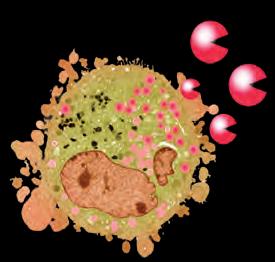

Rak krwi (białaczka)

Obraz komórki białaczki pod mikroskopem elektronowym. Nieustanne uwalnianie enzymów trawiących kolagen symbolizują czerwone “pacmany”.

Kiedy komórki raka zaczynają produkować enzymy „biologicznych nożyc”, pokonują wszelkie bariery i mogą atakować oraz powoli „trawić” struktury dowolnego organu naszego ciała.

Ma to miejsce także w przypadku komórek białaczki. Jedną z właściwości tej formy raka krwi jest to, że pacjenci chorujący na białaczkę nie umierają głównie, jak mogłoby się wydawać, z powodu nadprodukcji leukocytów, ale w wyniku blokowania przez nie przepływu krwi i zaczopowania funkcji organów.

W wielu przypadkach pacjenci umierają w wyniku niewydolności różnych organów, zwłaszcza organów „filtracyjnych”, takich jak wątroba czy śledziona. Miliony białych ciałek krwi dokonują inwazji tych organów z krwiobiegu. Nie przepływają one jednak po prostu przez owe organy, jak uczyniłyby to zdrowe leukocyty. Rakowe białe ciałka krwi wytwarzają duże ilości enzymów trawiących kolagen, dosłownie trawiąc te organy od wewnątrz.